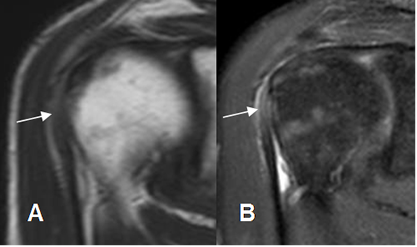

Fig 148. Tendinitis aguda de la cabeza larga del bíceps.

A: RM coronal en T1 y B: RM coronal en STIR. Tendón de la cabeza larga del biceps hiperintenso en T1 y STIR, por inflamación aguda.